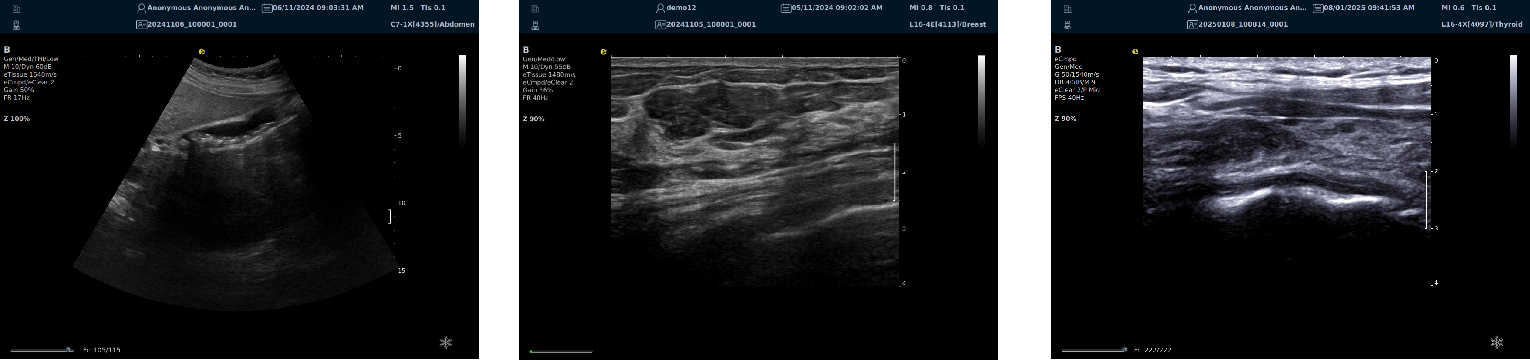

image.png

优异的二维图像